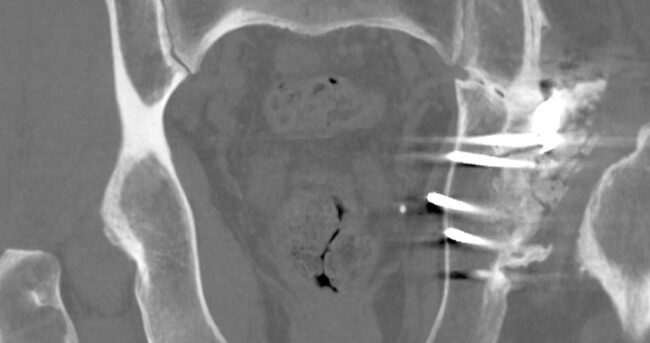

Podstawowym celem wszystkich zakładów radiologicznych powinno być dostarczenie wysokiej jakości usług diagnostycznych/zabiegowych przy zachowaniu możliwie najniższego ryzyka dla pacjenta. Niestety nie zawsze cele te są osiągane – błędy oraz zdarzenia niepożądane pojawiają się nawet w najlepszych organizacjach. Stąd niezwykle ważne jest, aby zakłady radiologii określiły potencjalnie „słabe” obszary i starały się redukować źródła błędów tak dalece, jak jest to możliwe.…